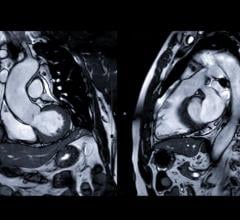

December 15, 2022 — An accepted manuscript published in ARRS’ American Journal of Roentgenology (AJR) guides ...